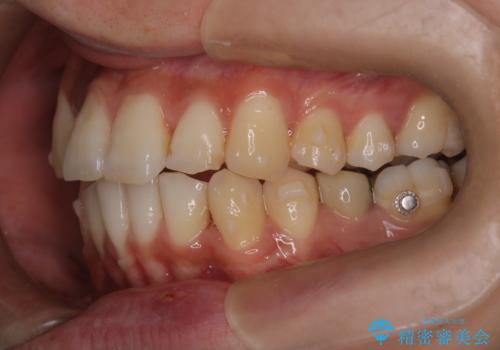

- 凸凹を治したいと来院された患者様です。

インビザラインにて、遠心移動を行いながら綺麗に配列することができました。

側切歯が低位の場合、反対咬合を改善した後に挺出させるのはワイヤーの方が適しています。